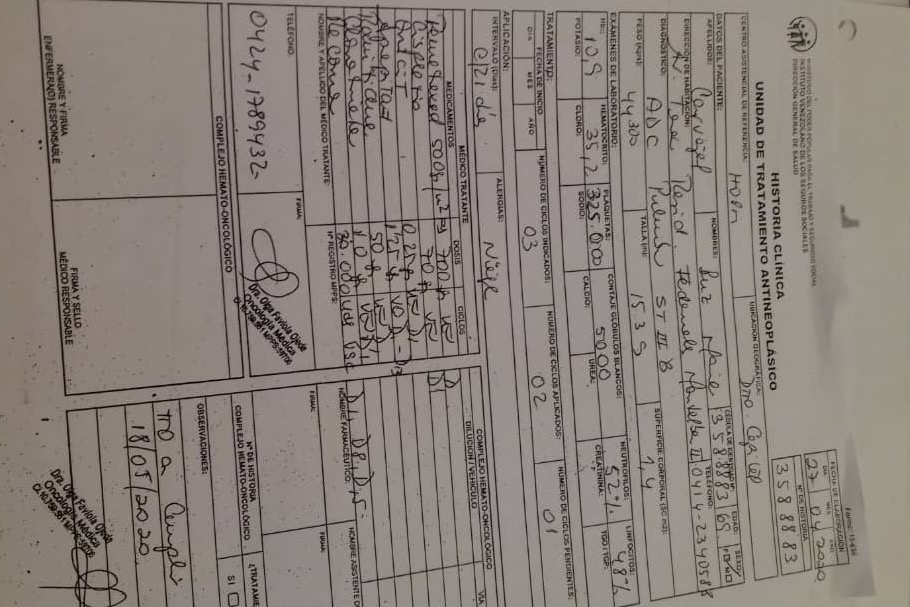

A través de varios familiares hemos logrado conseguir dinero para realizarle 36 ciclos de radioterapia y 6 de quimioterapia, además del tratamiento y todos los medicamentos requeridos hasta ahora, logrando una reducción importante del tamaño del tumor en pulmón en 40 %. Gracias a Dios la lesión en el mediastino se redujo también en un 80%.

Sin embargo, aún necesita varios ciclos de quimioterapia adicionales, un examen llamado PET Scan para verificar que no tiene alguna otra célula cancerígena en su cuerpo, una operación para extraer el resto del tumor, y tratamiento para acompañar todo el proceso que podría salvar su vida.

El dinero que pedimos es para costear los ciclos restantes de quimioterapia, el PET Scan, los medicamentos que acompañan todo el tratamiento y algunos gastos de movilización, debido a que me he visto en la necesidad de hacer una pausa en mi profesión y dedicarme a atender a mi mamá, trasladarla a sus tratamientos, quimioterapias, consultas, cocinarle, darle sus medicinas y acompañarla en las noches de dolor.

A continuación les dejo el diagnóstico, los exámenes, y los presupuestos de los próximos exámenes que hay que hacerle a mi mamá.

Through several family members we have managed to raise money to perform 36 cycles of radiotherapy and 6 of chemotherapy, in addition to the treatment and all the medications required so far, achieving a significant reduction in the size of the tumor in the lung by 40%. Thank God the injury to the mediastinum was also reduced by 80%.

However, she still needs several additional cycles of chemotherapy, a test called a PET Scan to verify that she doesn't have any other cancer cells in her body, an operation to remove the rest of the tumor, and treatment to accompany the entire process that could save her life. .

The money that we ask for is to pay for the remaining cycles of chemotherapy, the PET Scan, the medications that accompany the entire treatment and some mobilization expenses, due to the fact that I have seen the need to make a pause in my profession and dedicate myself to take care of my mother, to take her to her treatments, chemotherapies, consultations, cook her, give her medicines and accompany her on nights of pain.

Down here I leave the diagnosis, exams, and budgets for the next exams to be done to my mom.

A través de varios familiares hemos logrado conseguir dinero para realizarle 36 ciclos de radioterapia y 6 de quimioterapia, además del tratamiento y todos los medicamentos requeridos hasta ahora, logrando una reducción importante del tamaño del tumor en pulmón en 40 %. Gracias a Dios la lesión en el mediastino se redujo también en un 80%.

Sin embargo, aún necesita varios ciclos de quimioterapia adicionales, un examen llamado PET Scan para verificar que no tiene alguna otra célula cancerígena en su cuerpo, una operación para extraer el resto del tumor, y tratamiento para acompañar todo el proceso que podría salvar su vida.

El dinero que pedimos es para costear los ciclos restantes de quimioterapia, el PET Scan, los medicamentos que acompañan todo el tratamiento y algunos gastos de movilización, debido a que me he visto en la necesidad de hacer una pausa en mi profesión y dedicarme a atender a mi mamá, trasladarla a sus tratamientos, quimioterapias, consultas, cocinarle, darle sus medicinas y acompañarla en las noches de dolor.

A continuación les dejo el diagnóstico, los exámenes, y los presupuestos de los próximos exámenes que hay que hacerle a mi mamá.

Through several family members we have managed to raise money to perform 36 cycles of radiotherapy and 6 of chemotherapy, in addition to the treatment and all the medications required so far, achieving a significant reduction in the size of the tumor in the lung by 40%. Thank God the injury to the mediastinum was also reduced by 80%.

However, she still needs several additional cycles of chemotherapy, a test called a PET Scan to verify that she doesn't have any other cancer cells in her body, an operation to remove the rest of the tumor, and treatment to accompany the entire process that could save her life. .

The money that we ask for is to pay for the remaining cycles of chemotherapy, the PET Scan, the medications that accompany the entire treatment and some mobilization expenses, due to the fact that I have seen the need to make a pause in my profession and dedicate myself to take care of my mother, to take her to her treatments, chemotherapies, consultations, cook her, give her medicines and accompany her on nights of pain.

Down here I leave the diagnosis, exams, and budgets for the next exams to be done to my mom.